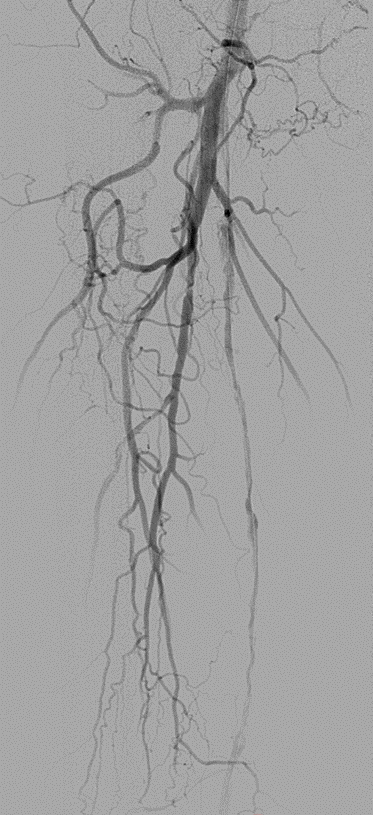

★ Case 1

noproximal stump in SFA,>250mm